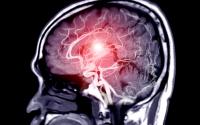

Brain MRI

Brain abnormalities could explain the confusion and delirium of severe COVID-19.